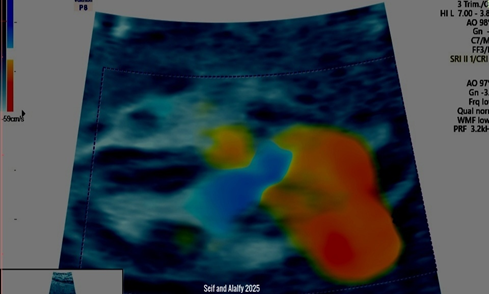

Seif and Alalfy twist sign, this technique describes an oblique view that illustrates the right and left ventricles with the interventricular septum and the atrioventricular valves with the aorta and pulmonary arteries crossing eachothers and till they form the v-sign ending to the ductus arteriosus as seen in Figure 1 and Figure 2.

Figure 2 Shows 3D US with Color Doppler illustrating Seif and Alalfy twist sign ,this technique describes an oblique view that illustrates the right and left ventricles with the interventricular septum and the atrioventricular valves with the aorta and pulmonary arteries crossing each others and till they form the v-sign ending to the ductus arteriosus.

This sign can be approached by sweeping the probe to get the optimum oblique view in the heart to illustrate right, left ventricles, interventricular septum, atrioventricular valves with the aorta and pulmonary arteries crossing each others.

The Seif and Alalfy twist sign can thus demonstrates a normal four chamber view and outflow tracts and 3 vessel views in a very short time Compared to the illustrated fetal echocardiography.